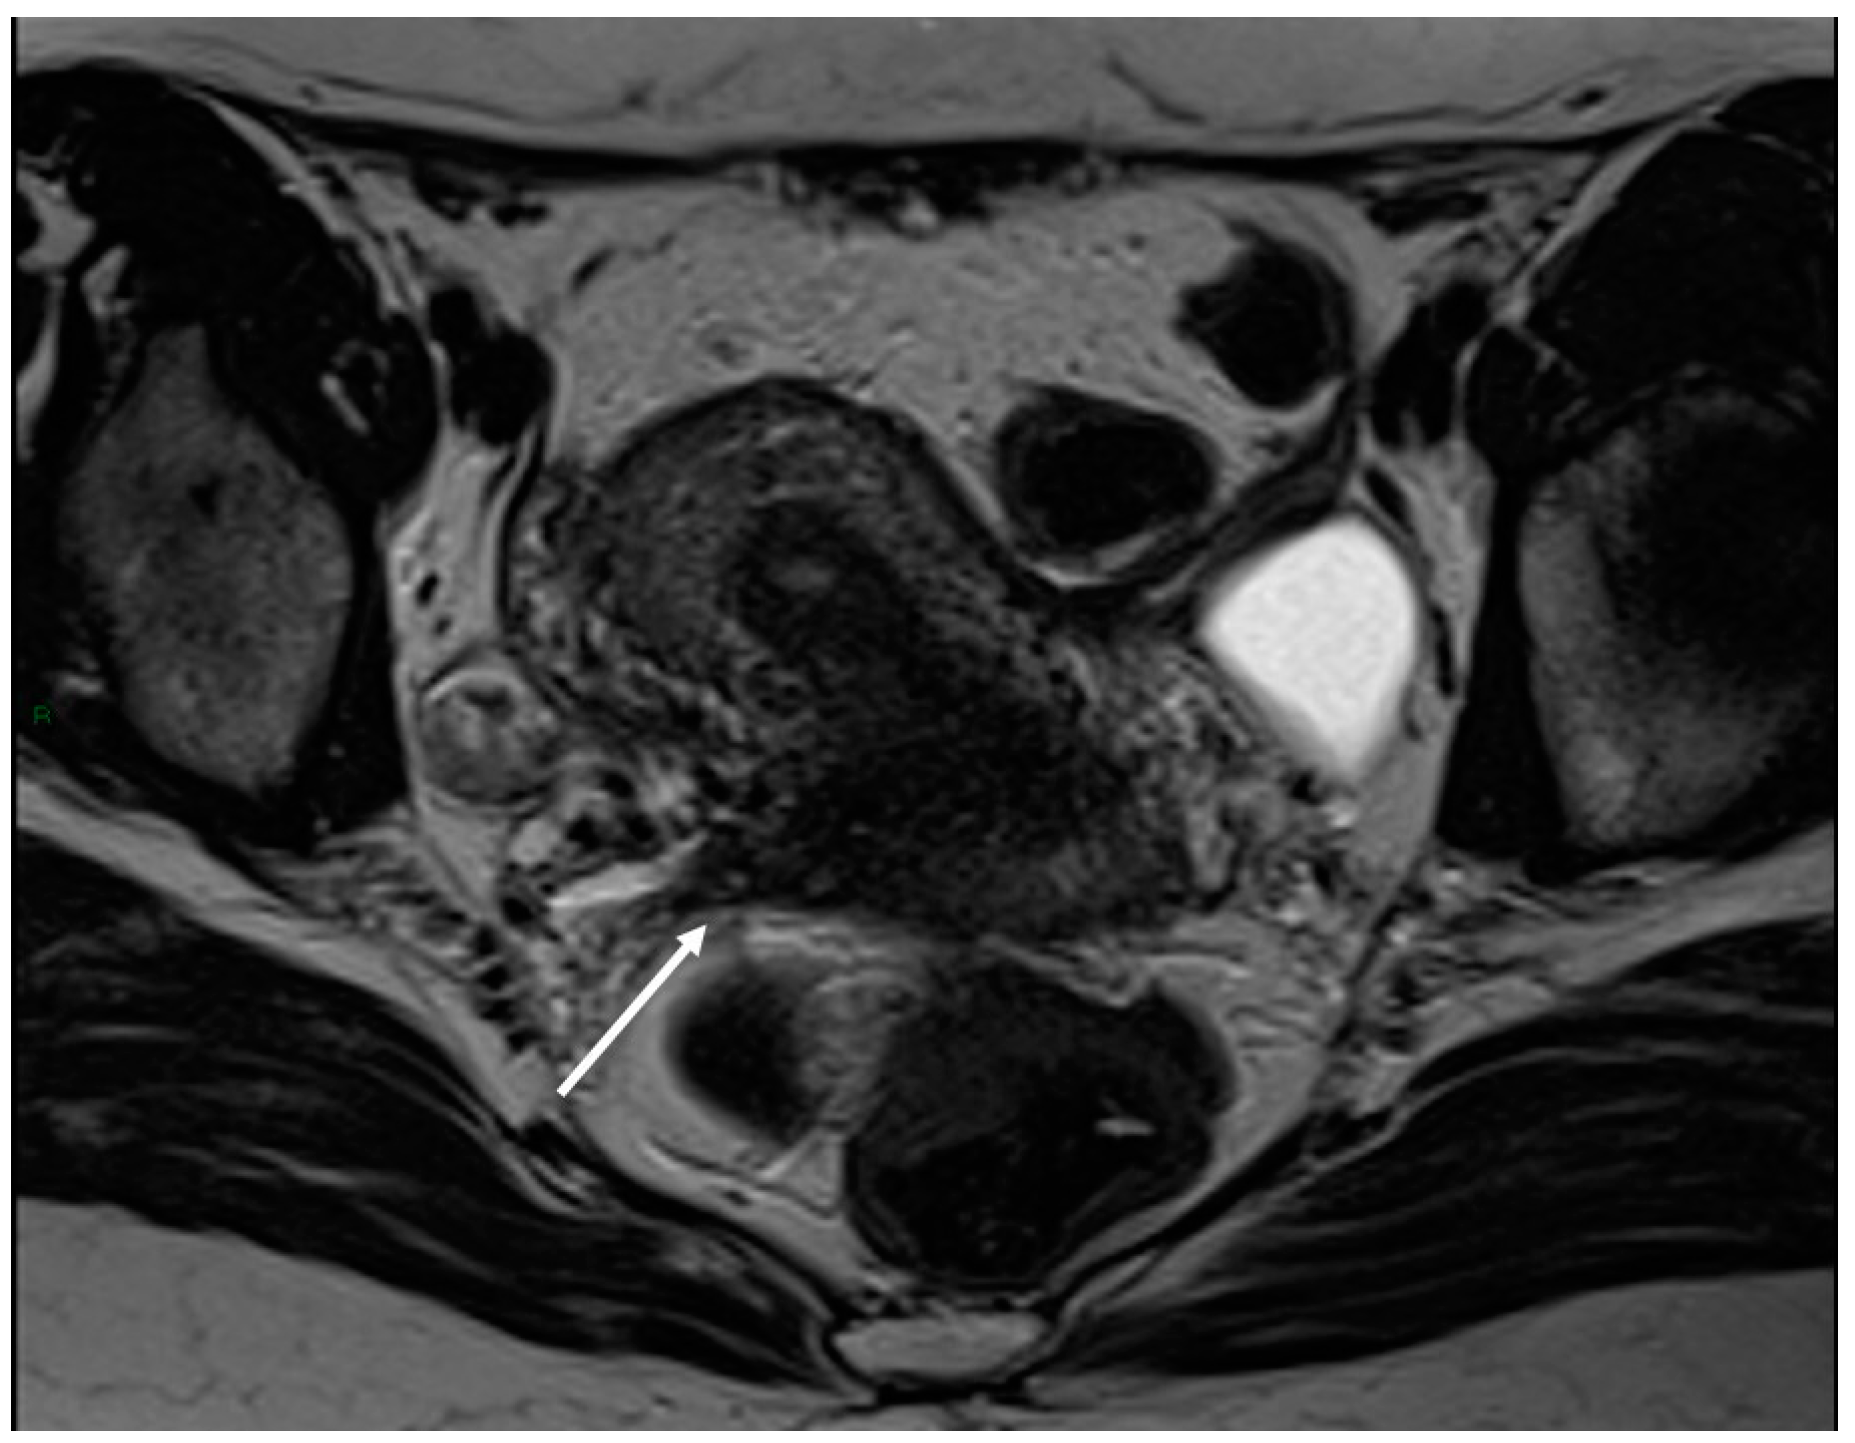

On an MRI, lesions appear as irregular thickness or nodules within the intestinal serosa or muscularis propria, hypointense at T2WI. They rarely affect the submucosa or the mucosa, and if infiltrated, we can observe edema and swelling in the area [7] (Figure 5 and Figure 6).

Figure 5.

External adenomyosis and intestinal endometriosis localization in 49-year-old female with story of multiple laparoscopy surgery. Sagittal T2WI shows a hypointense ill-defined subserosal mass in the posterior myometrium with hyperintense foci (long white arrow), suggestive for external adenomyosis, that cause retracting phenomena towards the anterior wall of the rectum. Additionally, there is deep endometriosis of the posterior compartment with hypointense nodule involving the serous and muscular layers of the anterior wall of the rectum (short white arrow).

Figure 6.

Retrocervical localization, intestinal mushroom cap sign and isthmocele in a 40-years old female. Retrocervical endometriosis localization (white dotted arrow), intestinal “mushroom cap sign” (white arrows) and isthmocele (black arrow).

What is also important for the radiologist to report, besides the depth and length of the plaques, is the distance between the lesion and the anal margin, as this can affect the type of surgery to be conducted [46]. In severe cases, the MRI shows a circular involvement resulting in a clinical condition of occlusive or sub-occlusive stenosis [47].